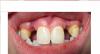

Bier Опубликовано 15 октября, 2013 Поделиться Опубликовано 15 октября, 2013 Сфотографируйте как выглядит это сейчас Ссылка на комментарий

Заринка Опубликовано 16 октября, 2013 Автор Поделиться Опубликовано 16 октября, 2013 Ссылка на комментарий

Заринка Опубликовано 17 октября, 2013 Автор Поделиться Опубликовано 17 октября, 2013 А обычным фотоаппаратом? Так как мою вторую тему закрыли, напишу здесь свою вторую проблему. Через неделю после снятия швов на на правой стороне образовался свищ, врач три раза промывал (один раз разрезал, а потом промывал проколами) стало лучше, 11.10.2013г. появилась шишка на левой стороне вверху, не могла даже улыбаться (тянуло десну). С 14.10.2013г. каждый день проколами врач промывает эту сторону. Назначен уже третий вид антибиотиков и полоскание хлоргексидином. В связи с чем может быть это воспаление? Боюсь, что воспаление пойдет в кость и импланты нужно будет удалить... Врач пока ничего не говорит! Ссылка на комментарий